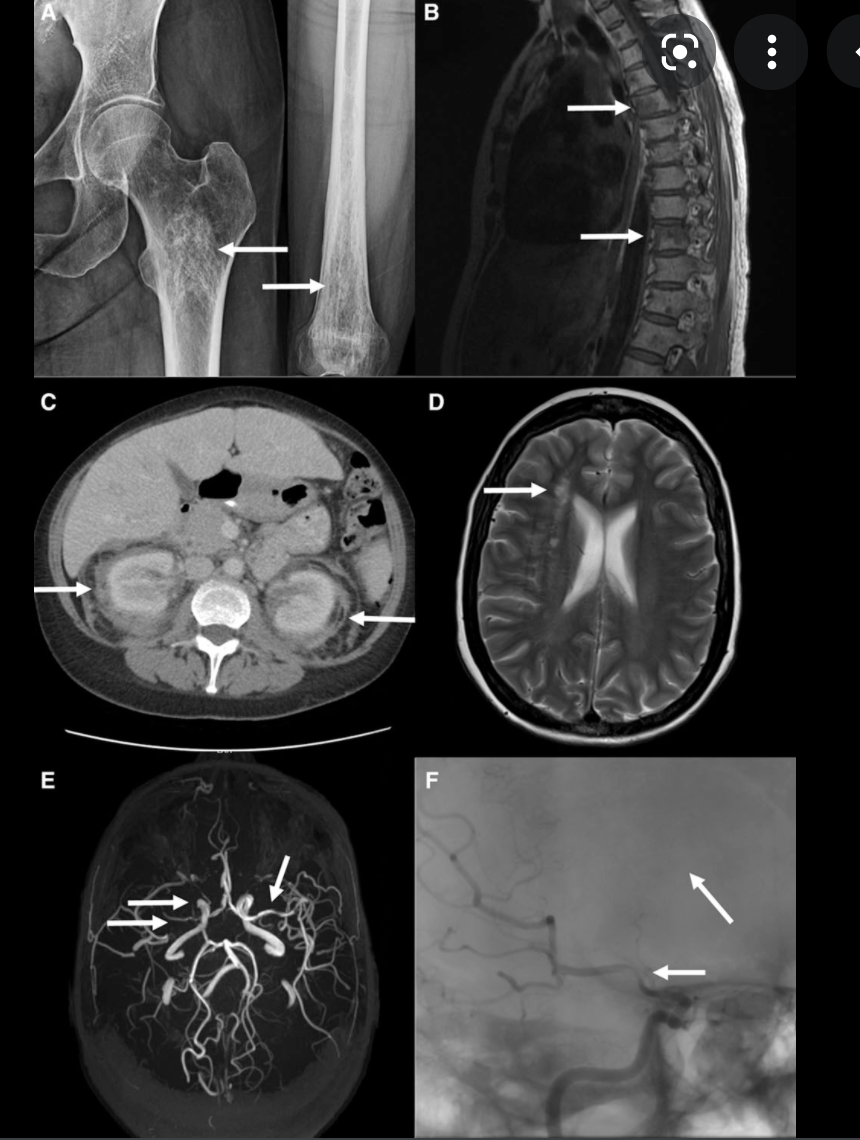

Sturge-Weber syndrome, or encephalotrigeminal angiomatosis, is a phakomatosis characterised by facial port wine stains and pial angiomas.

Approximately a third of patients have choroidal or scleral angiomatous involvement, which may be complicated with retinal detachment, buphthalmos or glaucoma 1.

Bilateral Sturge-Weber syndrome. Postcontrast axial MR image ( A ) shows gross leptomeningeal thickening and enhancement related to the right hemisphere and less extensive abnormality of the left occipital region. Unenhanced axial T1-weighted image ( B ) shows thickening of the posterior globes bilaterally; after administration of contrast material ( C ), marked enhancement is seen in both globes. Abnormal high signal is present in this region on the proton density–weighted image ( D ). Bilateral, diffuse choroidal hemangiomas were found at ophthalmoscopy (not shown).